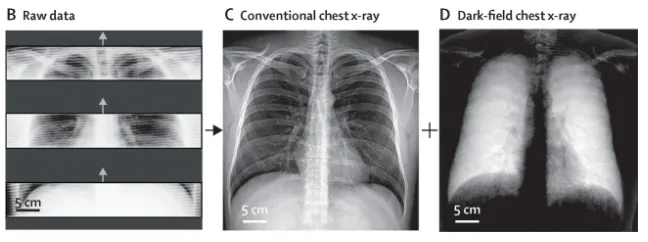

Figure . Examples of raw detector imaging data (B), retrieved conventional chest x-rays (C), and dark-field chest x-rays (D) from the first in-human application